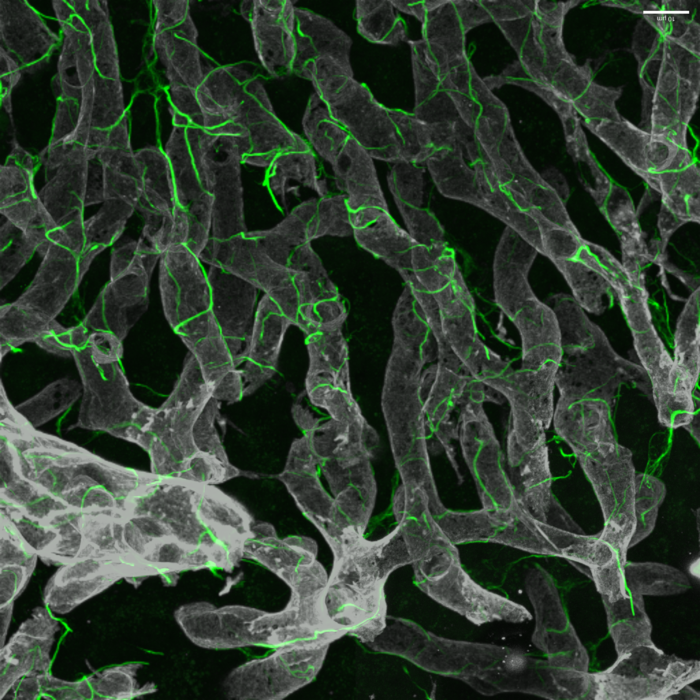

在健康的肝臟中,肝臟星狀細(xì)胞及其復(fù)雜的細(xì)胞投影(綠色)包裹在血管(灰色)周?chē)?/strong>

利用最新的技術(shù)——包括小鼠和人類(lèi)肝組織的單核測(cè)序和先進(jìn)的小鼠3D玻璃成像來(lái)表征關(guān)鍵的產(chǎn)生瘢痕的肝細(xì)胞——研究人員發(fā)現(xiàn)了治療非酒精性脂肪性肝病(NAFLD)的新的候選藥物靶點(diǎn)。這項(xiàng)研究是由西奈山伊坎醫(yī)學(xué)院的研究人員領(lǐng)導(dǎo)的。

“我們的目的是了解這種纖維化瘢痕的基礎(chǔ),并通過(guò)研究肝星狀細(xì)胞(肝臟中關(guān)鍵的瘢痕生成細(xì)胞),確定可能導(dǎo)致晚期NASH新治療方法的藥物靶點(diǎn),”高級(jí)研究作者Scott L. Friedman博士說(shuō)。“結(jié)合這種新的玻璃肝臟成像方法——一種先進(jìn)的組織清除方法,能夠深入洞察——以及單個(gè)星狀細(xì)胞的基因表達(dá)分析,我們對(duì)這些細(xì)胞如何在NASH進(jìn)展到晚期時(shí)產(chǎn)生瘢痕有了全新的理解?!?/p>